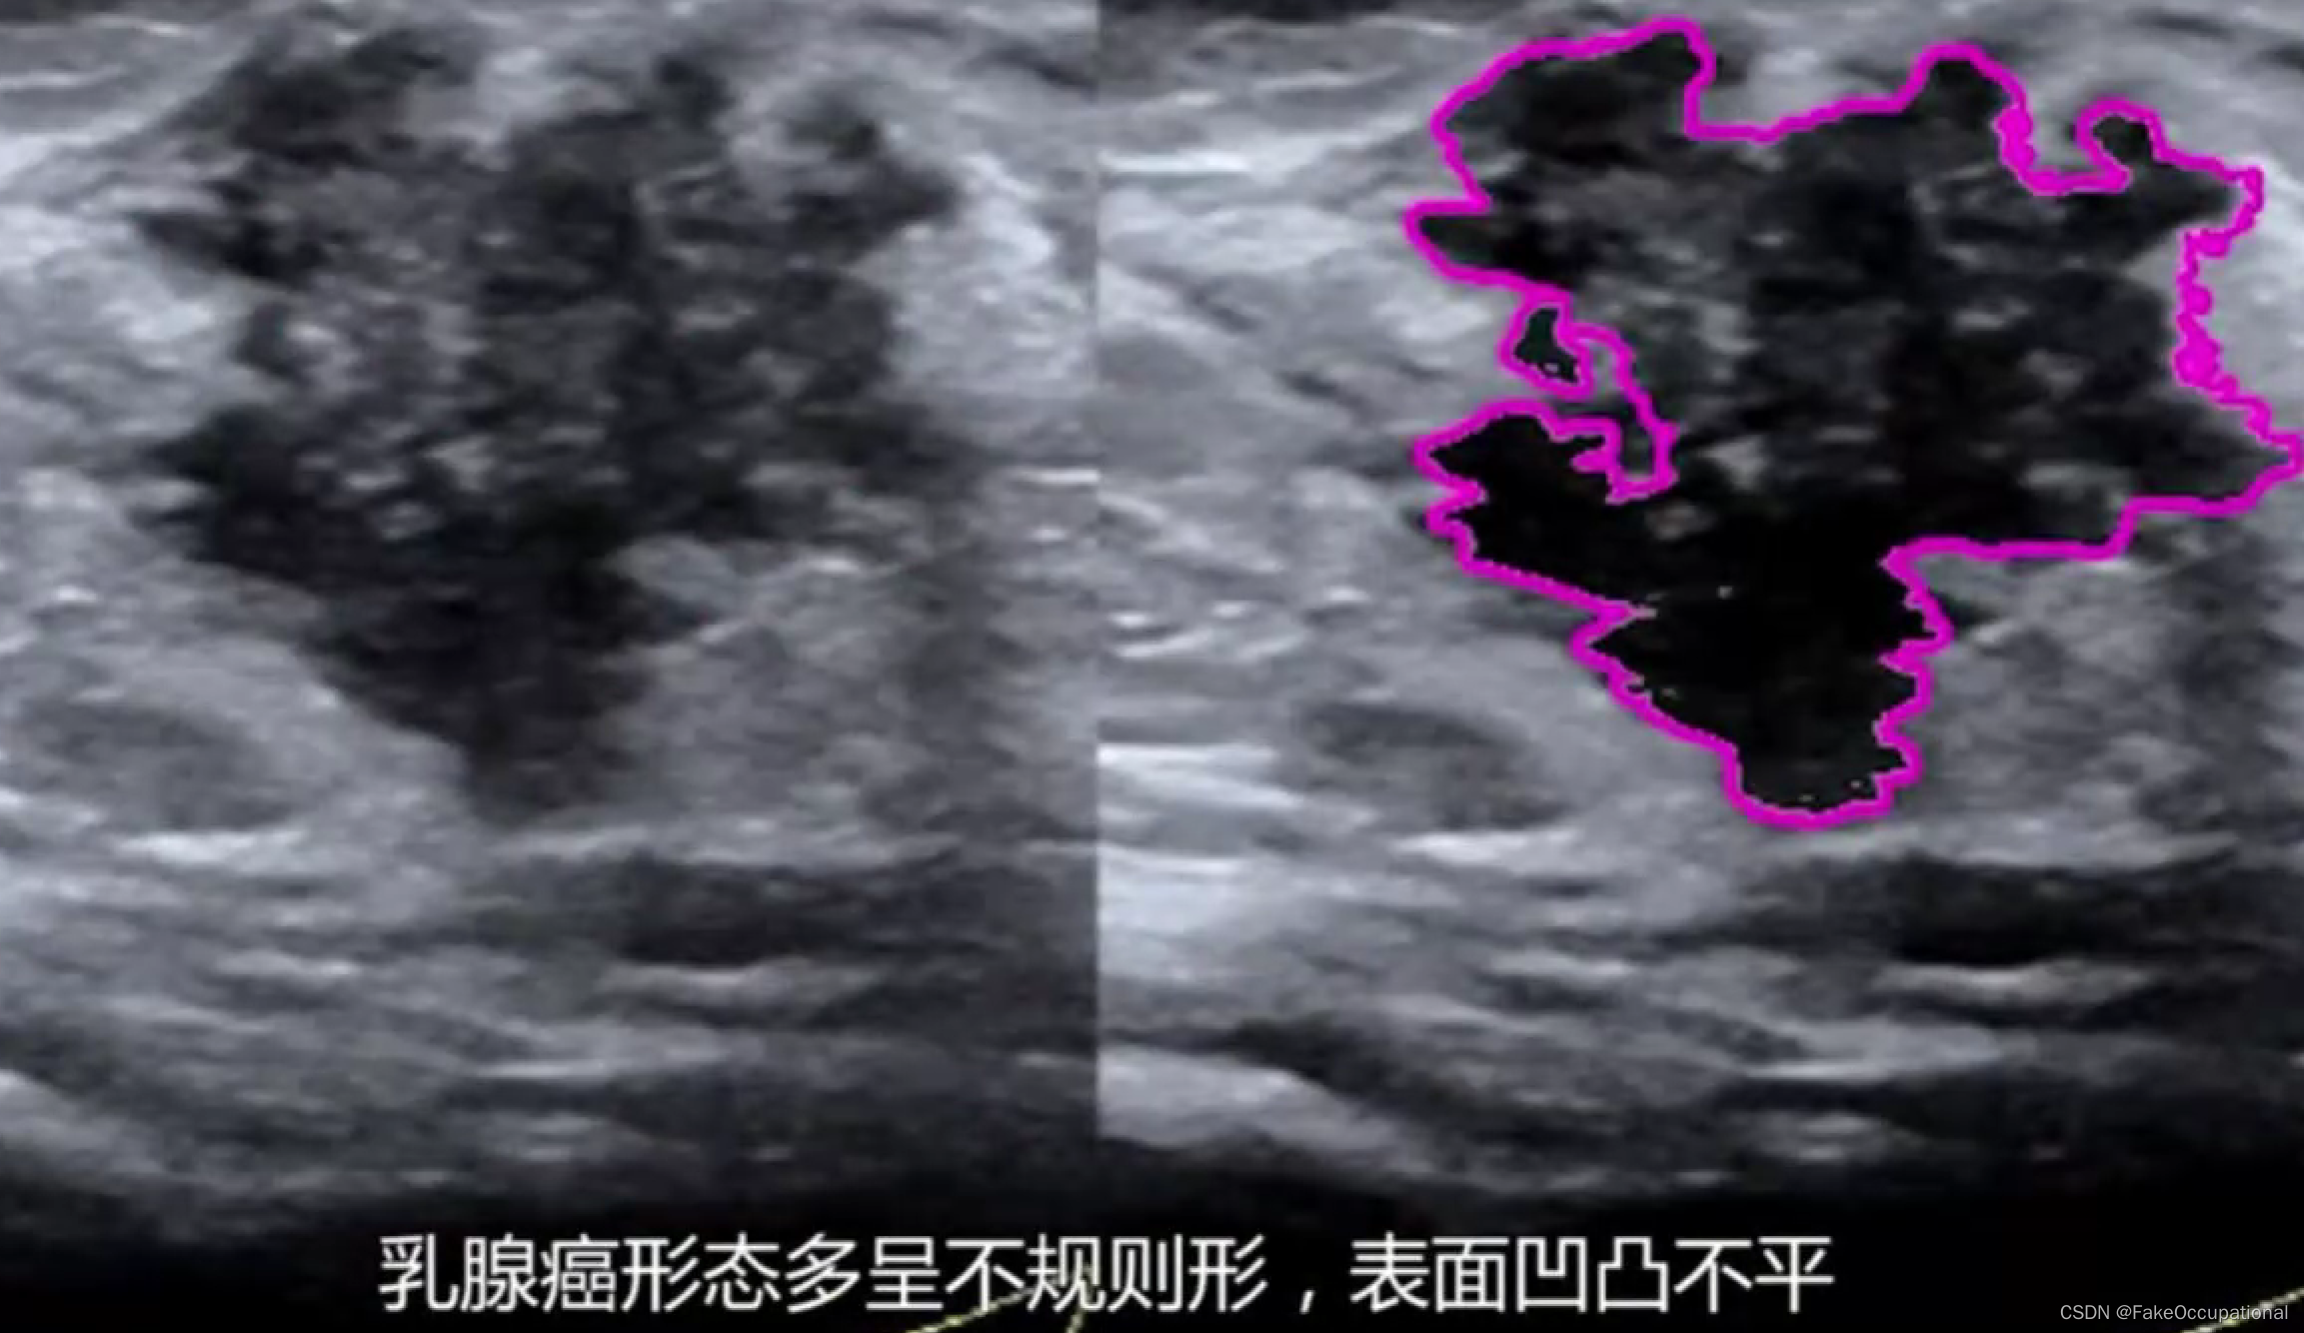

乳腺癌